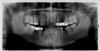

Сергей 79 Опубликовано 26 октября, 2009 Автор Поделиться Опубликовано 26 октября, 2009 Извините, но фото нет. Выкладываю ОПГ. На консультации уважаемый доктор сказал, что при системе Danon 3 "быстрые" брекеты, в моём случае, после соответствующей подготовки (удаление старых протезов и лечение) подготовка к имплантации займёт 5-7 месяцев. Ссылка на комментарий

krasik Опубликовано 26 октября, 2009 Поделиться Опубликовано 26 октября, 2009 Подготовка к имплантации в Вашем случае - это закрытие промежутков и создание места под импланты. , В принципе это можно успеть сделать за 6 месяцев (хотя с трудом). Но это еще не все ортодонтическое лечение. На этом этапе можно поставить импланты и пока они приживляются, продолжить и закончить ортод.лечение. Ссылка на комментарий